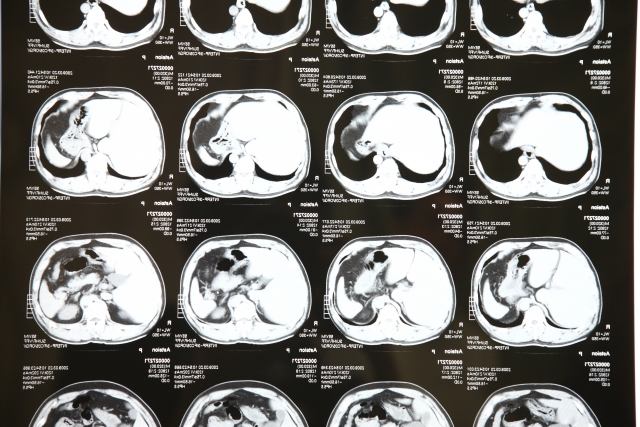

腹膜播種とは、がん細胞が腹膜の表面にまるで種をまいたかのように散らばって広がる状態を指します。CTなどの画像検査で診断を試みますが、すべての病変が画像に映るとは限りません。この記事では、腹膜播種がCTで見つけにくい理由や、補助的に用いられる検査法、そして治療の選択肢を解説します。

播種病変がある程度の大きさになると、CTなどの画像検査でも明瞭な腫瘤として描出されるようになります。ただし、CTによる腹膜播種の検出には限界があり、微小な病変は見逃される可能性があります。

また、大腸がんの腹膜播種では、播種結節が0.5cm未満では同定率が11%、5cm以上であれば94%だったとする報告もあります。つまり、病変の大きさによってはCTで検出できない場合もあり、それが腹膜播種がCTに写りにくい理由と考えられます。

一般的には、造影CT検査や、PET/CT検査、MRI、超音波などの検査が、腹膜播種の検出のために行われています。

造影CT検査は、ヨード造影剤を静脈注射し、CT画像を撮影することで、がんなどの病変や血流の有無などをより詳細に調べることができます。